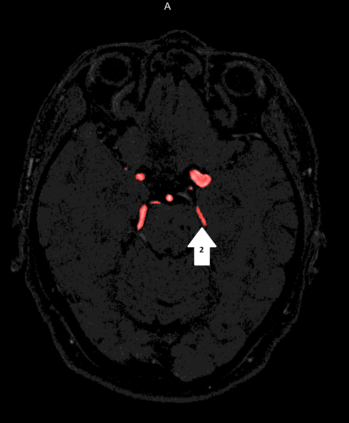

Deep learning approaches may help radiologists in the early diagnosis and timely treatment of cerebrovascular diseases. Accurate cerebral vessel segmentation of Time-of-Flight Magnetic Resonance Angiographs (TOF-MRAs) is an essential step in this process. This study investigates deep learning approaches for automatic, fast and accurate cerebrovascular segmentation for TOF-MRAs. The performance of several data augmentation and selection methods for training a 2D and 3D U-Net for vessel segmentation was investigated in five experiments: a) without augmentation, b) Gaussian blur, c) rotation and flipping, d) Gaussian blur, rotation and flipping and e) different input patch sizes. All experiments were performed by patch-training both a 2D and 3D U-Net and predicted on a test set of MRAs. Ground truth was manually defined using an interactive threshold and region growing method. The performance was evaluated using the Dice Similarity Coefficient (DSC), Modified Hausdorff Distance and Volumetric Similarity, between the predicted images and the interactively defined ground truth. The segmentation performance of all trained networks on the test set was found to be good, with DSC scores ranging from 0.72 to 0.83. Both the 2D and 3D U-Net had the best segmentation performance with Gaussian blur, rotation and flipping compared to other experiments without augmentation or only one of those augmentation techniques. Additionally, training on larger patches or slices gave optimal segmentation results. In conclusion, vessel segmentation can be optimally performed on TOF-MRAs using a trained 3D U-Net on larger patches, where data augmentation including Gaussian blur, rotation and flipping was performed on the training data.